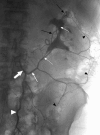

The arterial and venous circulation of the bowel is complex and is characterized by marked redundancy of multiple interconnecting branches, which provides a rich blood supply to aid in the digestive process and also serves to protect the bowel from potential ischemia or infarction. As a result of this circulatory pattern, anatomic variants and extensive collateral pathways are common. A thorough knowledge of both the arterial and venous mesenteric circulation, including normal, variant, and collateral anatomy, is necessary for the appropriate evaluation and management of the various disease processes that may affect the vascular supply of the gastrointestinal system.